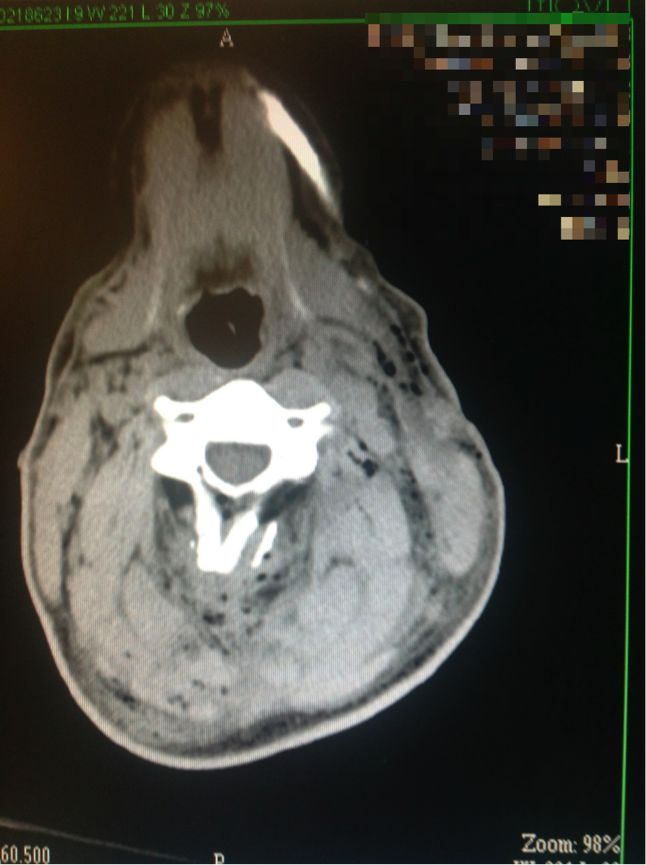

These next images show the path of the bullet through the neck, and the vital structures that the bullet somehow didn’t disrupt. Also included is an anatomy slide taken from the Internet, showing the gross structures at roughly the same level for comparison. In the first image, the path of the bullet can be seen by the small pockets of air drawn into the tissues as the bullet passed through, which appear black on the CT image. A blue line has been drawn along the bullet’s rough path to illustrate. The next image was taken after a dye was injected in the casualty’s veins, which pumped around his blood vessels, causing them to appear white on the CT scan.

Mentally superimposing the path of the bullet, it can be seen that it passes directly through a rather large pipe in the front of the casualty’s neck, which I assess as being the internal jugular vein. (I’m very happy to be corrected by any radiologists out there!) Immediately next to the internal jugular vein is an even more important structure, the internal carotid artery, which, had it been disrupted, would have almost certainly resulted in the death of the casualty given the circumstances on the day. Miraculously, neither of these major blood vessels were damaged, with the only rational explanation offered by the treating surgeon being that the bullet simply pushed them aside. Once again, in my opinion, were this to have been a M4 round, I suspect the outcome would have been dramatically worse.